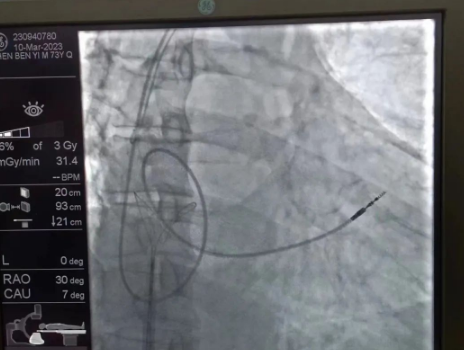

術(shù)中,孫書紅醫(yī)師首先切開起搏器囊袋,游離出起搏器脈沖發(fā)生器,發(fā)現(xiàn)起搏電極完全斷裂,連接于起搏脈沖發(fā)生器,殘端約10cm;考慮患者為起搏依賴患者,需再次植入新的起搏電極導(dǎo)線,穿刺了腋靜脈,放置導(dǎo)絲;同時,李偉杰教授穿刺了左、右股靜脈,于右股靜脈置入了”抓捕器”,左股靜脈備用臨時起搏通路,以防術(shù)中出現(xiàn)心跳驟停。為了準(zhǔn)確抓捕到心房內(nèi)的在逃起搏電極,李偉杰教授將導(dǎo)管室的X光機(jī)球管調(diào)整成了冠脈模式,這就意味著在抓捕過程中,醫(yī)生要比平時的手術(shù)“吃”更多射線……

在透視模式下,抓捕全憑醫(yī)生的經(jīng)驗與手感,一次次嘗試,一次次失敗,在場外觀摩手術(shù)的醫(yī)生同樣為李偉杰教授捏了一把汗,“找到了!”電子屏里抓捕器向在逃起搏電極“發(fā)起進(jìn)攻”,一把逮住并順利拔出一根長達(dá)58cm的起搏電極。